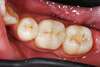

Lorsqu’une dent est trop abîmée pour être réparée par un simple composite, mais pas suffisamment atteinte pour nécessiter une couronne complète, les inlays et onlays en céramique représentent une solution de choix.

Ces restaurations partielles, fabriquées sur mesure, permettent de reconstituer avec précision la partie manquante de la dent, tout en préservant au maximum sa structure naturelle.

Les inlays et onlays en céramique sont des restaurations dentaires haut de gamme, parfaitement adaptées aux dents fragilisées par une carie profonde ou une ancienne obturation. Bien plus qu’un simple "plombage", ils offrent une alternative intelligente à la couronne ou aux gros composites.